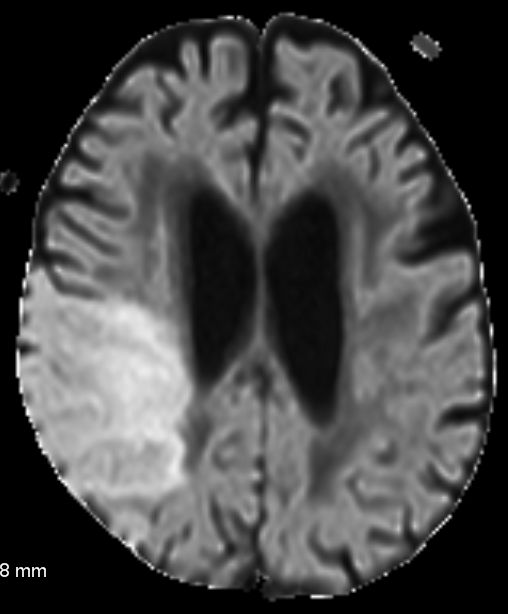

MRT spezielle Sequenzen für den Apoplex: DWI,PWT 76-jähriger Mann mit frischem Apoplex. Ausfall des hinteren Mediabereiches rechts. MR DWI og tra Sense

MR DWI EADC

DWI Diffusion weighted imaging